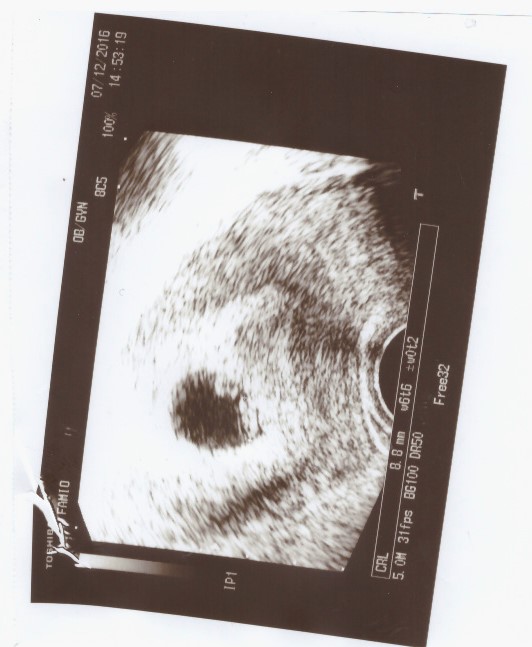

Ahoj, byla jsem dnes první kontrole, takže máme první foto. Jsem pultrazvuku teprve 6+6, ale vzhledem mu, že budu rodit jako 37 letá, chce doktor, abych šla určitě na odběr plodové vody, což se mě moc nechce. Jaké prosím máte argumenty pro nebo proti. Podotýkám ještě, že máme zdravého jednoletého synka.

Díky, foto v příloze.